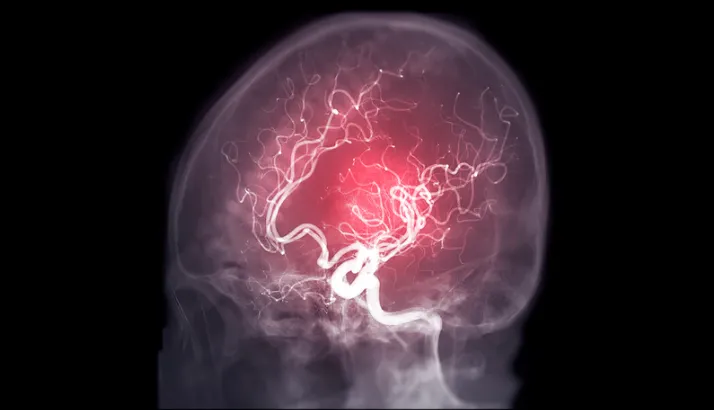

Hace solo un par de días se dio a conocer que el animador Leo Caprile sufrió un infarto cerebrovascular (ACV), pero que gracias a una rápida actuación y a una atención médica oportuna evitaron que sufriera consecuencias graves y de mayores complicaciones. Es en este contexto que el manejo de los síntomas y de ciertas características pueden alertarte de sufrir un ACV.

Jorge Valdés, director del Diplomado en Neurorrehabilitación Fonoaudiológica de la Universidad San Sebastián, enfatizó en la importancia de reconocer aquellos signos de alerta y el pronto actuar con el fin de minimizar el daño causado por un ACV y, si bien los síntomas puedes ser variados, algunos signos de cambio repentino como la movilidad, sensibilidad, el habla, visión, así como mareos, confusión o dolor de cabeza intenso son síntomas que no hay que dejar pasar.

“Si alguien reconoce debilidad o adormecimiento de un lado del cuerpo, dificultades de visión en uno en ambos ojos, dificultades para hablar o comprender el lenguaje, dolor de cabeza, vértigo o inestabilidad es fundamental buscar atención médica de inmediato”, indica el profesional.